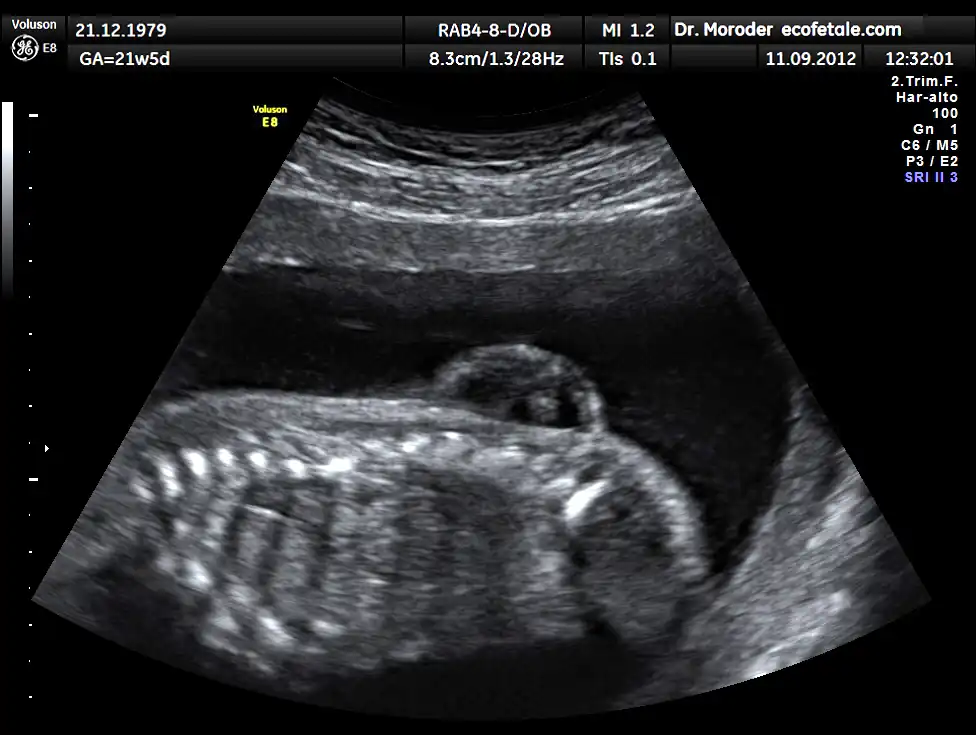

![]() Imagen ultrasonido de columna feto 21 semanas con espina bífida | ||